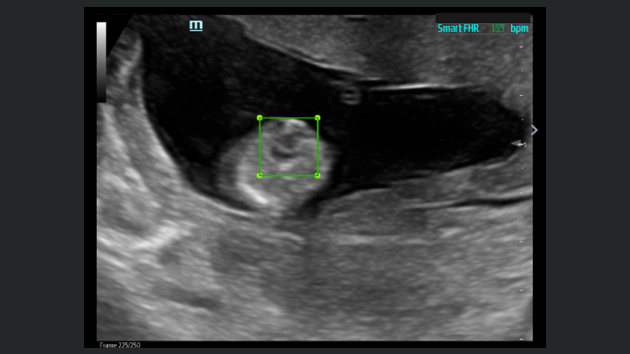

The TE9 Ultrasound System is designed to expand imaging capabilities across point-of-care environments including anaesthesia, emergency, and critical care.

A large clear touchscreen, superior imaging and intelligent diagnostic tools allow the TE9 to support clinical efficiency and diagnostic confidence in high acuity settings. Its compatibility with a wide range of transducers means it can easily adapt to meet point-of-care needs and support a wide range of procedures and diagnostics.

Images

Transducers